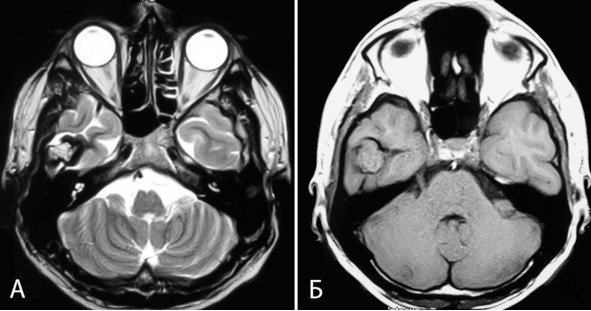

Чемпионка России по академической гребле в юношеской группе. В 2002г появилась интенсивная головная боль, снизилось зрение. Лечилась по месту жительства, КТ, МРТ не производились, выписаны очки. Через 2 месяца зрение восстановилось. В марте 2006г появились легкие нарушения статики и походки. В августе 2006г вновь появилась головная боль и ухудшение зрения. Лечилась с диагнозом «Вегето-сосудистая дистония». 4.09.06 упала на улице, сознания не теряла. 12.09.06 выполнена КТ головы, при которой выявлены множественные объемные образования мозга, выраженная гидроцефалия с перивентрикулярным отеком. Направлена в институт, где при МРТ 25.09.06 выявлены множественные каверномы головного мозга: кавернома правой ножки мозга и таламуса с распространением в III желудочек и частичной окклюзией сильвиева водопровода, признаками кровоизлияния; небольшие каверномы правой лобной доли и левой височной доли (рисунок 24: А, Б, В). При обследовании родственников каверномы также выявлены у отца и дочери пациентки (рисунок 24: Д). 3.10.06 больная госпитализирована в институт. Неврологический статус при поступлении: выраженная общемозговая симптоматика в виде сильной головной боли, заторможенности; мезенцефальные симптомы, экстрапирамидные симптомы в правых конечностях, выраженные нарушения статики и походки.

Учитывая тот факт, что ведущими в клинической картине являются симптомы окклюзионной гидроцефалии, а удаление каверномы среднего мозга и таламуса сопряжено с высоким риском нарастания очаговой симптоматики, 10.10.06 выполнена перфорация дна III желудочка. В ходе операции через эндоскоп была хорошо видна субэпендимальная кавернома (рисунок 24, Г). В послеоперационном периоде отмечен постепенный регресс общемозговых симптомов.

Рисунок 24. А, Б, В – МРТ б-ной К. Диагноз: множественные каверномы (3) головного мозга. А – кавернома полюса правой лобной доли (режим Т2, аксиальная проекция). Б – кавернома ножки мозга и таламуса, окклюзионная гидроцефалия (режим Т1, аксиальная проекция). В – кавернома левой височной доли. Виден также фрагмент каверномы среднего мозга справа (режим Т2, аксиальная проекция). Г – кавернома среднего мозга, вид на эндоскопической операции (премоторный доступ слева): 1 —субэпендимальный фрагмент каверномы в проекции водопровода мозга, 2 – таламусы, 3 – левая гипоталамическая борозда, 4 – эпиталамическая спайка, 5 – межталамическое сращение. Д – МРТ отца больной: субкортикальная кавернома правой височной доли (режим Т2, аксиальная проекция). Катамнез: периодически обращается в институт для контрольного обследования, последнее обращение – 21.09.10. Состояние стабильное, ведет активный образ жизни. Сохраняется мягкая мезенцефальная симптоматика. МРТ – без динамики. Случай демонстрирует возможность успешного лечения связанной с каверномой окклюзионной водянки, путем выполнения шунтирующей операции.